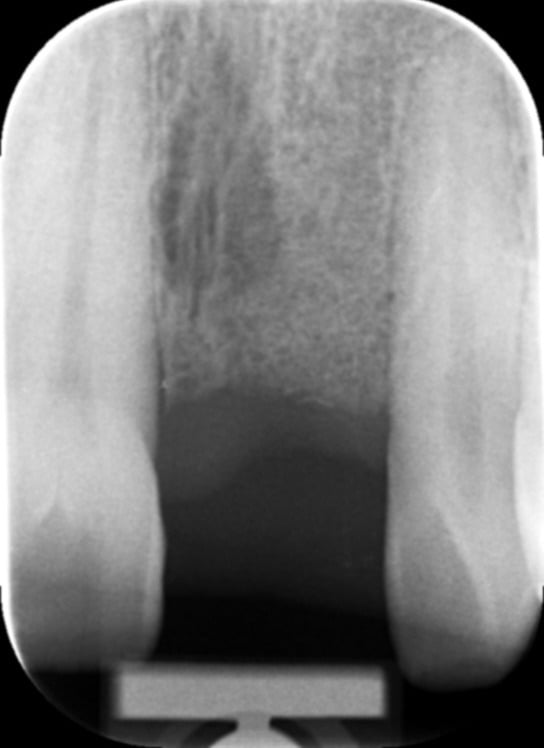

The fixture (titanium screw) replaces the function of a natural tooth root. Your jawbone attaches to the titanium threads of the fixture, providing a completely stable foundation for the new crown – a process known as osseo-integration. It usually takes twelve weeks for the bone to securely bond to the entire fixture surface.

Your natural teeth are stable biting and chewing surfaces because your jawbone supports them. This is also true of dental implants. Successful dental implants become firmly embedded in the jaw through osseointegration, a natural process where the bone grows onto the implant surface.